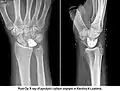

Fig 2. Kienbocks x-ray Fig 2. Kienbocks x-ray

Kienbock’s Disease is defined as avascular necrosis of the lunate (Cross & Matullo, 2014, p. 141). The direct cause of Kienbock’s disease is largely unknown (Almquist, 1986, Nathan & Meadows, 1987) however, studies have confirmed an association between negative ulnar variance and the development of Kienbock’s Disease (Bonzar et al., 1998, Mirabello, Rosenthal, & Smith, 1987). Subjective information shows that ROM tests and palpation cause the patient a large amount of pain. It was identified that the most comfortable position for the client to be in is a supported, resting position. This is supported by Rizzo (2008, p. 491) by stating that avascular necrosis of the carpus is an important cause of wrist pain, limited motion, and weakness.